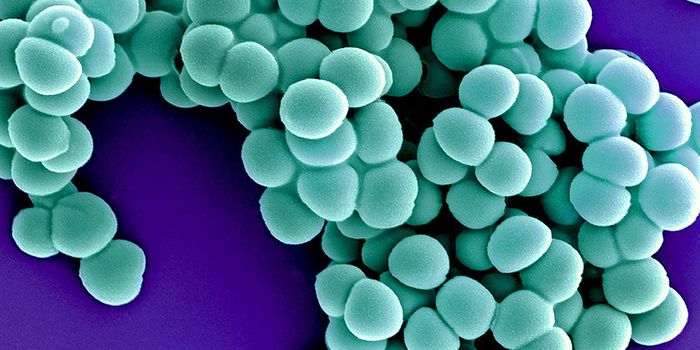

APR 18, 2025MicrobiologyPathogenic bacteria are getting deadlier because they are increasingly gaining resistance to crucial antibiotics. Whole ...

MAR 30, 2025Cell & Molecular BiologyBacteria can easily evolve, and can quickly gain resistance to drugs. Drug-resistant bacterial infections already cause ...